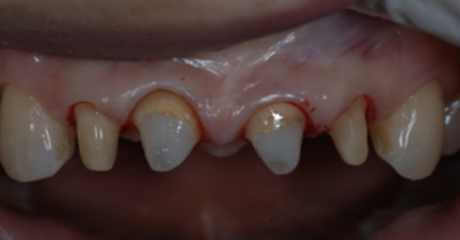

신경치료 후 남아있는 치질이 너무 짧거나 부족한 경우

크라운을 씌우기 전 치아안쪽에 기둥을 세우고 보강해주는 과정이 필요합니다.

치아의 길이가 너무 짧은 경우는 치아의 길이를 늘리는 수술이 필요하기도 합니다.